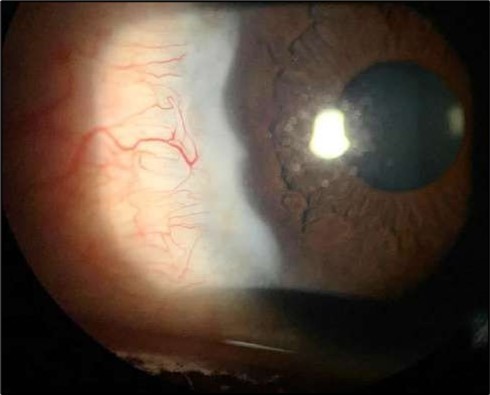

At six-months follow-up post-resection, the ulcer showed progressive epithelialization with no recurrence. Oral prednisolone was gradually tapered and stopped. The patient remains under regular ophthalmology follow-up with stable ocular findings Figure 6.

Figure 6.Six-month follow-up image showing a stable ocular surface, and absence of ulcer recurrence. The cornea appears clear centrally, with stromal scarring limited to the periphery.

Six-month follow-up image showing a stable ocular surface, and absence of ulcer recurrence. The cornea appears clear centrally, with stromal scarring limited to the periphery.